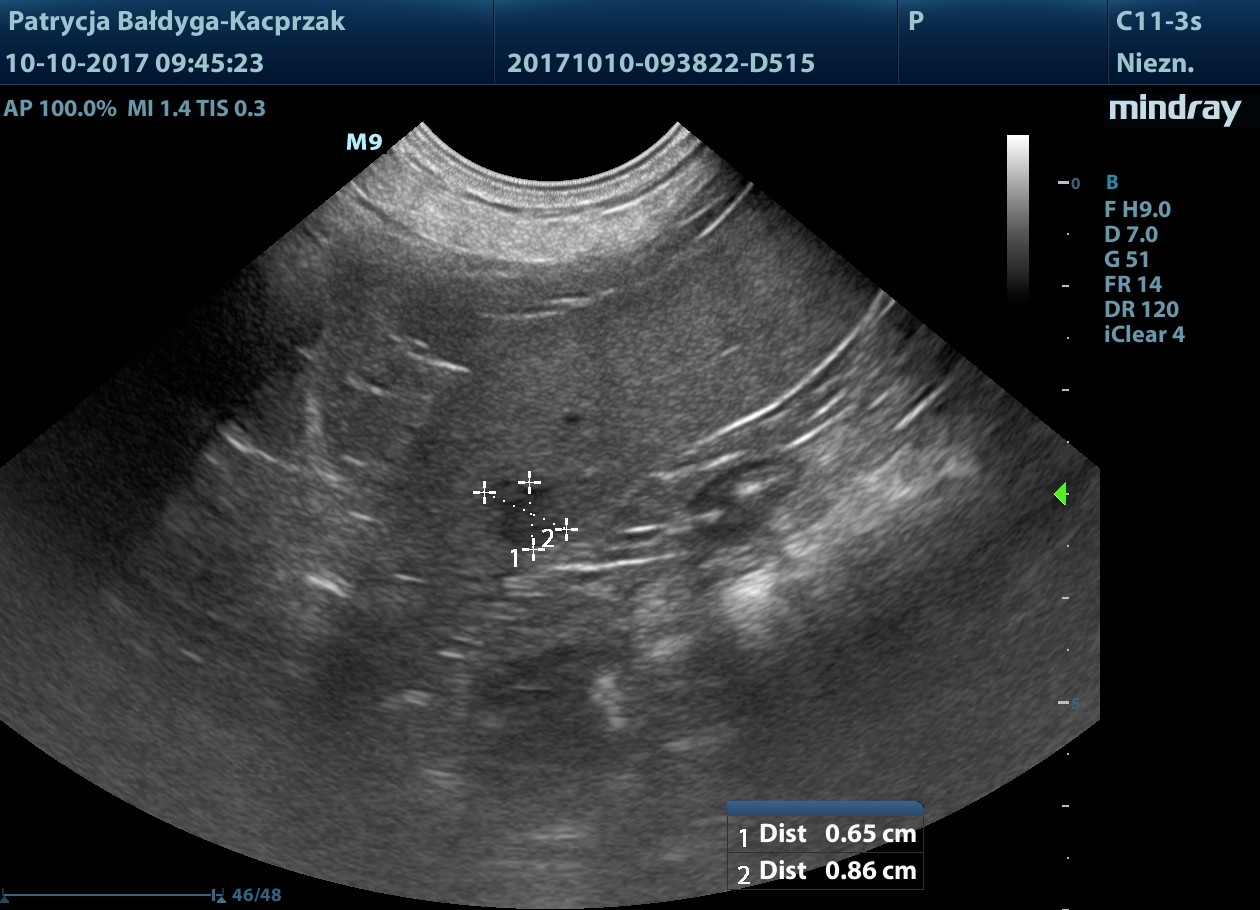

Śledziona niepowiększona, miąższ nieco niejednorodny zobecnością zawnękowo, przyściennie zmiany ogniskowej

słabo odgraniczonej, nieco hipoechogennej w centrum, hiper obwodowo, wielk. ok. 1,2 cm, mniejsza widoczna przedwnękowo, od pow. trzewnej, podtorebkowo śr. ok. 6-8 mm

niejednorodnie hipoechogenna, nieregularna, zmiany nie modulują brzegu narządu, bez cech patognomicznych.